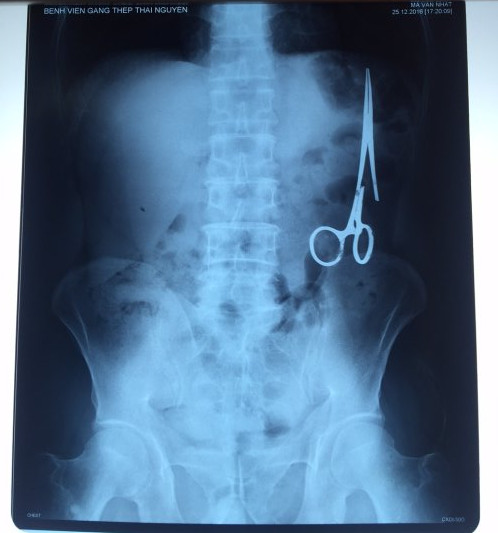

遺留在病人腹中的剪刀

據(jù)越南青年報1月2日報道,在越南首都河內(nèi)醫(yī)療專家的幫助下,越南東北部的太原?。═hai Nguyen)鑄鋼醫(yī)院的醫(yī)生日前從54歲患者M.V.N腹中取出一把醫(yī)用剪刀。這把剪刀是此前曾為M.V.N手術(shù)的醫(yī)生遺留的,已經(jīng)在其腹中待了18年時間。

醫(yī)務(wù)人員表示,這把剪刀遺留在病人腹部左側(cè),與結(jié)腸緊挨著。剪刀的把手已經(jīng)生銹,部分器官也已經(jīng)與剪刀粘連起來。但在過去多年中,M.V.N沒有任何不適感覺,也從未因為留在腹中的剪刀引發(fā)的相關(guān)問題去看過醫(yī)生。直到2016年12月,M.V.N因為遭遇了一場車禍,才到鑄鋼醫(yī)院進行身體檢查。

超聲波檢查顯示,M.V.N的腸子中有個奇怪物體,看起來就像醫(yī)用剪刀。M.V.N證實,他曾于1998年6月份在北江省綜合醫(yī)院接受手術(shù),在此后也從未進行過任何手術(shù)。近來,他感到腹部有些疼痛,并試圖通過服用藥物治療。12月27日,M.V.N回到北江省綜合醫(yī)院再次進行超聲波檢查,顯示其腹部的確存在怪異物體。